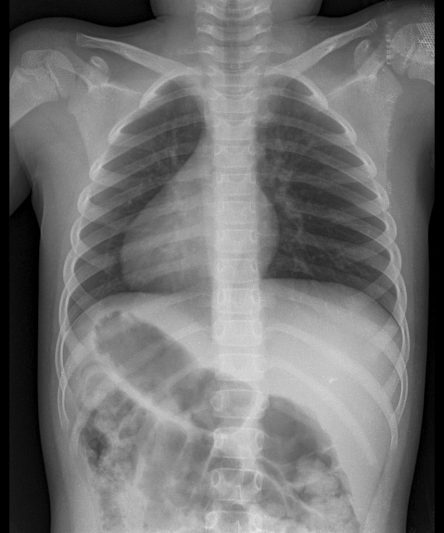

Microskan with Ultra high frequency can take the Lateral Lumbar Spine image of a 90 kg Patient with the correct image receptor